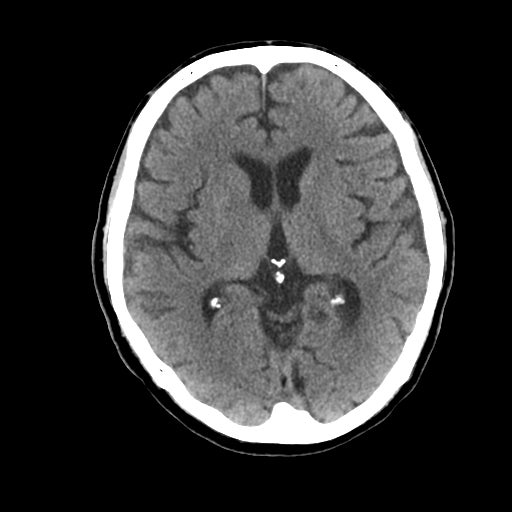

2-1. 低吸収領域の検出・表示例(下)

頭部CT検査において、周囲に比べ白く映る部分(高吸収領域)が見られる場合には、脳出血が疑われます。脳出血は高血圧・脳腫瘍・脳血管の異常などが要因となり、脳の動脈が破れて脳内部に出血した状態を指します。一方、周囲に比べ黒く映る部分(低吸収領域)が見られる場合には、脳梗塞が疑われます。脳梗塞は、脳内の血管が詰まるなどにより血液の流入が止まり、脳に酸素や栄養が行き渡らなくなる状態です。また、急性期の脳梗塞では、頭部CT検査において、灰白質と白質の境界が消失するなどの所見(ECS=early CT sign)が見られ(2)、こうした所見を見落とさずに治療につなげることが肝要です。